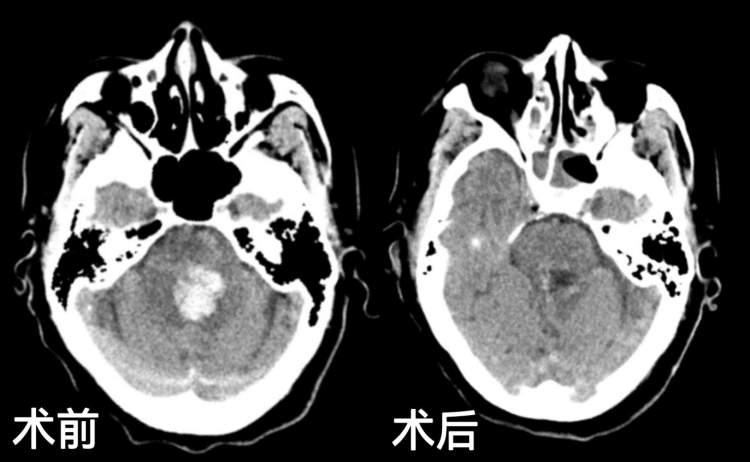

术中,机器人辅助系统精准定位脑干血肿位置,按设计好的手术路径,将接触性内镜引流导管经皮层送入脑干血肿腔,整个过程实时清晰呈现操作视野,术者在严密监护下稳步操作,成功抽吸血肿15毫升,整个手术过程顺利,未出现术中并发症。

术后复查头颅CT显示,王奶奶颅内引流管位置理想,脑干血肿清除效果满意,各穿刺道均无出血,手术达到预期效果。